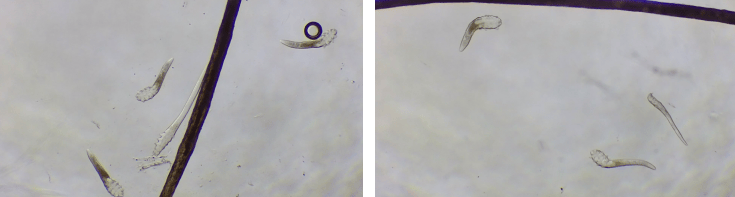

武汉普瑞眼科医院角膜及眼表疾病科徐静医生为婆婆进行了详细检查,发现其睑板腺存在萎缩,并伴轻度干眼症。而在显微镜下,婆婆的睫毛根部居然蜗居了20多只蠕动的螨虫,看得人头皮发麻。

该院医生介绍道,这些螨虫体长仅0.1-0.4毫米,肉眼难以察觉,它们多寄生在睫毛根部和睑板腺内,其代谢产物会堵塞毛囊及睑板腺开口,导致眼红、眼痒、眼干、眼部灼烧感、异物感、畏光、分泌物增多等症状;可伴有反复睫毛脱落、睫毛乱生,以及过敏性结膜炎、睑缘炎、睑缘结膜炎等;严重时可累及角膜,造成视物模糊、视力下降。